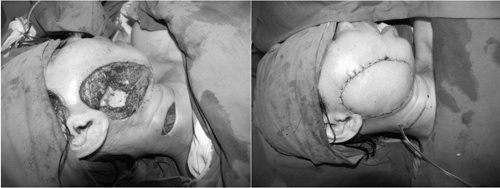

| Di chứng xạ trị (trái) được tạo hình bằng vạt tự do. |

Trường hợp khuyết hổng lớn dưới kỹ thuật vi phẫu phải dùng vạt tự do hoặc các vạt có chân nuôi để phục hồi lại các khuyết hổng tổ chức. Sau đó, nếu cần thiết sẽ phải tiếp tục phẫu thuật tạo hình lại bộ phận bị hỏng, giúp bệnh nhân có khuôn mặt bình thường để trở lại cuộc sống.